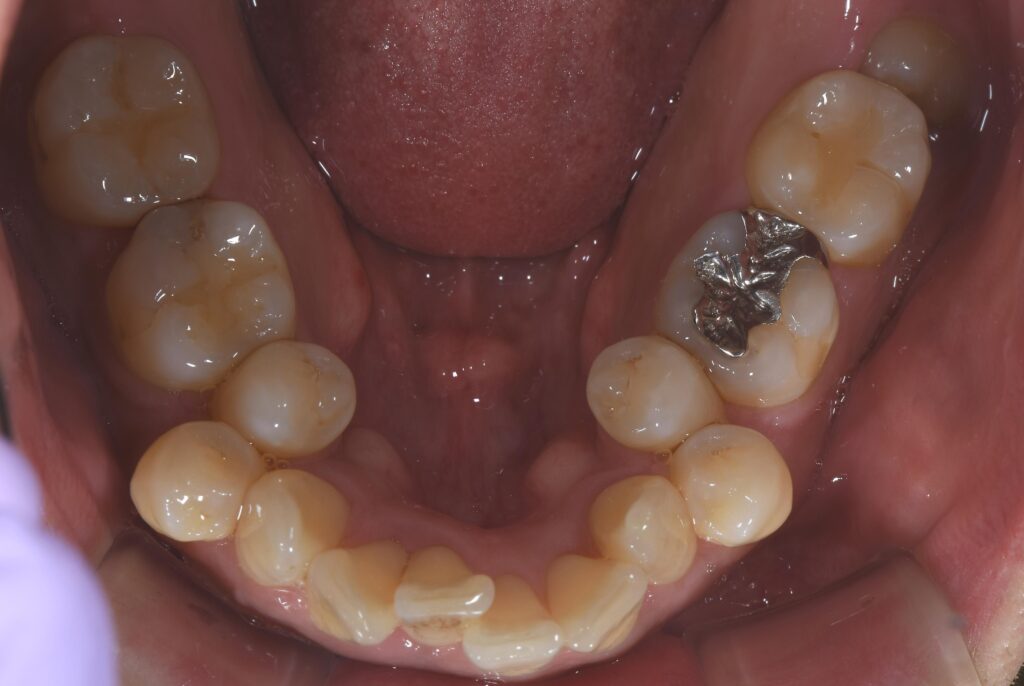

【初診時の状態】

歯のがたつきを認め、スペースの獲得のため左右の小臼歯(前から数えて4番目の歯)を抜歯しました。